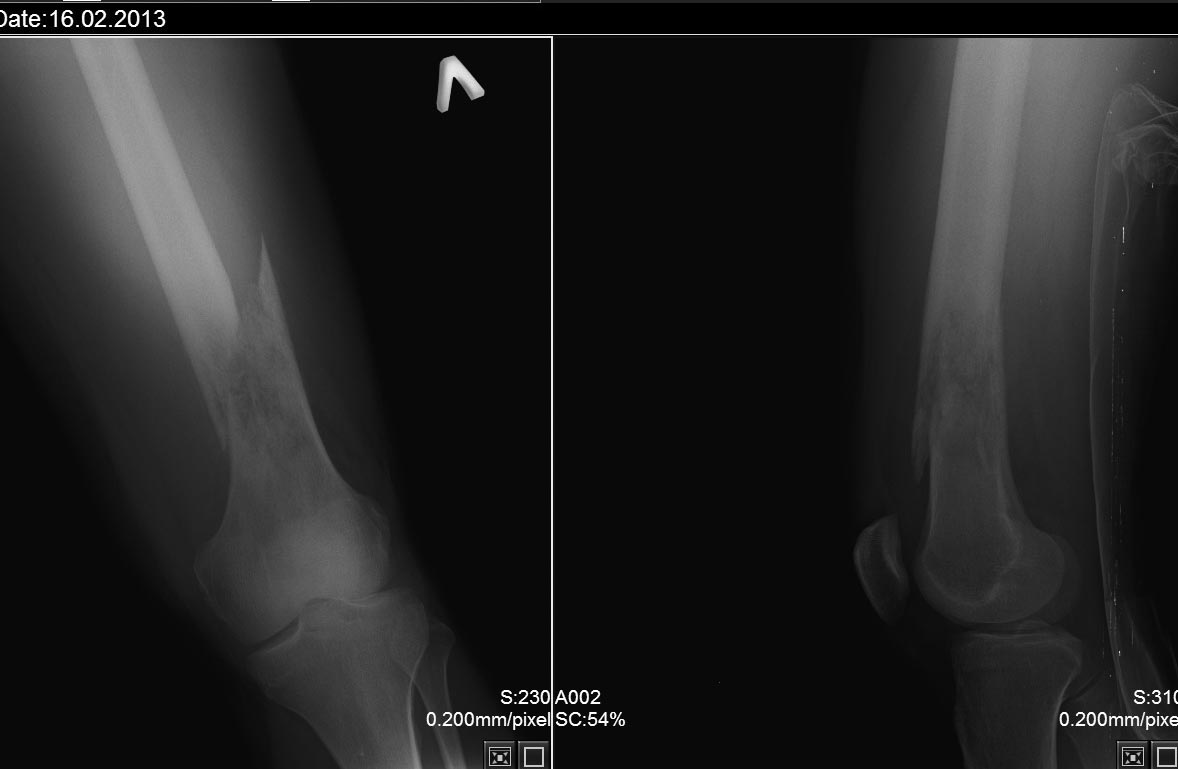

остеогенная саркома бедра?

16.02.13поступил молодой человек 26 лет с переломом бедра.Травма при падении на улице. Ранее отмечал боли в коленном суставе поврежденной , лечился у ревматолога с синовитом. В настоящее время проводится ДСВ. Хотелось бы узнать мнения о диагнозе и где лучше оперировать такого пациента.

ИМХО, на остеосаркому не похоже.

Дифдиагноз включает саркому (Юинга, остеосаркому, MFH of bone и другие), лимфому и инфекцию. Как упомянуто доктором Adonin, ортопед-онколог, который будет в дальнейшем лечить пациента, должен сделать биопсию. МРТ мало поможет сейчас, так как гематому от перелома будет трудно отличить от самой саркомы. В случае, что это саркома, перелом лечится в гипсе и даётся химия. Если перелом срастается после химии, что случается в 80-90 процентах случаев, то потом следует сделать МРТ и провести удаление саркома с реконструкцией конечности. Если перелом не срастается, то потребуется ампутация. В случае лимфомы, перелом можно фиксировать пластиной и потом делать химию и возможно радиацию. Но сначала следует сделать биопсию, чтобы установить диагноз и проверить на метастазы.